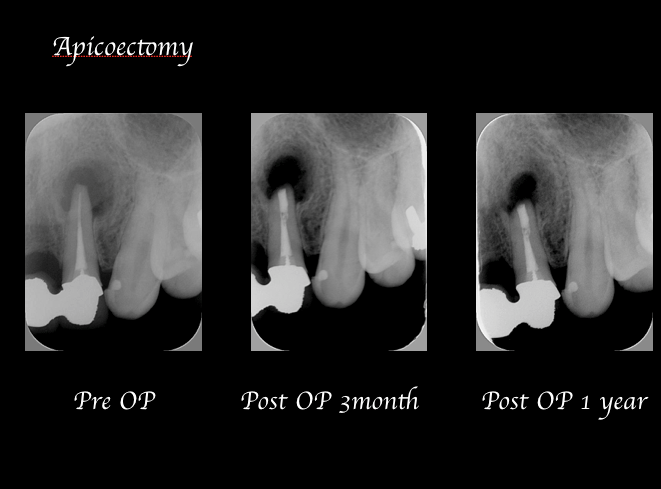

歯根端切除術症例2|術後1年をかけて病変の透過像がゆっくり縮小

一方で、以前私が歯根端切除術を行った症例ですが、下記症例2の写真より、左上2番の歯根端切除術後、1年で透過像の消失までは至っていないケースです。

しかしながら、術直後より歯肉の腫脹や痛みが改善されたのをはじめ、1年をかけて病変の透過像も非常にゆっくりではありますが縮小してきているのがわかります。

この時点では治癒傾向がみられますが、こういった症例では、引き続き経過観察を行い完全治癒、もしくは失敗に移行しないかを注意深く経過観察しレントゲン写真を撮影していくことが必要となるのです。